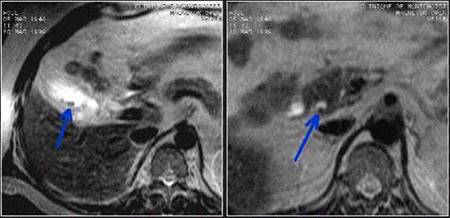

1.3.6-Risonanza magnetica

Con

Nelle seguenze T2 pesate è possibile invece vedere presenza di calcoli, liquido pericolecistico e ascessi intramurali. 11 , 12

Fig 6 Risonanza Magnetica addome superiore . aumento dello spessore di parete della colecisti e presenza di formazioni litiasiche